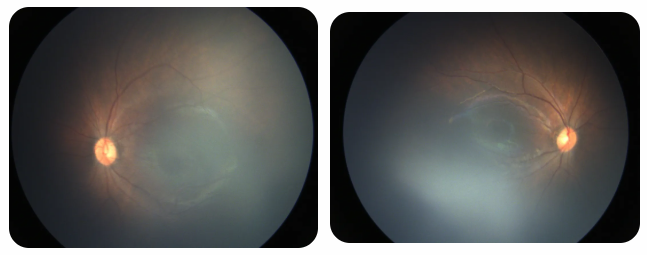

廈門(mén)眼科中心黎曉新名醫(yī)工作室曾接診一名31周出生的早產(chǎn)兒,出生體重僅1300克。由于家長(zhǎng)缺乏篩查意識(shí),直到孩子5個(gè)月大時(shí)眼睛仍不會(huì)追光,才前來(lái)就診。檢查發(fā)現(xiàn),患兒ROP已進(jìn)展至4B期,因纖維血管增殖牽拉導(dǎo)致視網(wǎng)膜脫離,錯(cuò)過(guò)了最佳治療窗口。盡管黎曉新教授團(tuán)隊(duì)成功實(shí)施了玻璃體切割手術(shù),孩子的視力仍存在不可逆損傷。此后,孩子開(kāi)啟了長(zhǎng)期隨診復(fù)查、治療的“護(hù)眼征程”,目前其右眼矯正視力為0.6,左眼為0.8。

近期術(shù)前檢查:

早產(chǎn)兒視網(wǎng)膜病變

術(shù)后復(fù)查:

相比之下,另一位早產(chǎn)寶寶在出生5周后,生命體征穩(wěn)定之時(shí),便在產(chǎn)科醫(yī)生的建議下轉(zhuǎn)診至廈門(mén)眼科中心。經(jīng)篩查確診為Ⅲ期ROP,黎曉新教授團(tuán)隊(duì)及時(shí)為其進(jìn)行了激光治療。半年后復(fù)查顯示,寶寶的視網(wǎng)膜血管發(fā)育正常,視力發(fā)育與足月兒童無(wú)異。